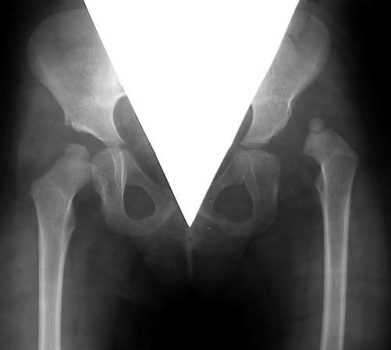

Дисплазия - это врожденный дефект строения ТБС, для которого характерна неправильная ориентация суставных компонентов. Дисконгруэнтность головки бедренной кости и вертлужной впадины приводит к функциональной перегрузке определенных частей сустава. Постоянная механическая травматизация вызывает дегенеративные изменения в суставных хрящах, капсуле и субхондральных костных структурах. В результате у больного развивается ранний деформирующий остеоартроз.

Тяжелая степень дисплазии.